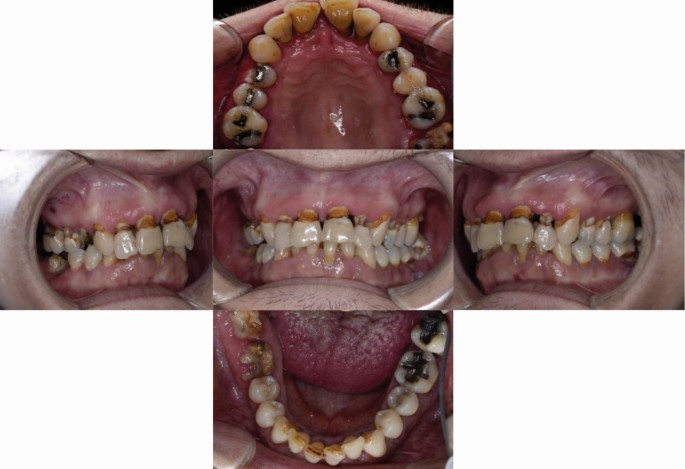

Extraoral examination revealed cutaneous pallor, multiple tattoos, finger clubbing, and weight loss (BMI = 16.1). Intraoral examination revealed mucosal pallor, moderate mouth dryness according to the Challacombe scale,17 chronic plaque-induced gingivitis, extensive cervical caries involving most teeth, and badly broken unrestorable lower right first and second molars, upper second molar, and upper first premolar (Fig. 1). Radiographic examination, including orthopantomogram (OPG) and full mouth periapical radiographs, revealed extensive cervical caries, impacted lower third molars on both sides, generalised horizontal alveolar bone loss consistent with chronic periodontitis, and furcational involvement of upper and lower molars (Fig. 2). The upper left and right lateral incisors were judged to be non-vital and unrestorable.